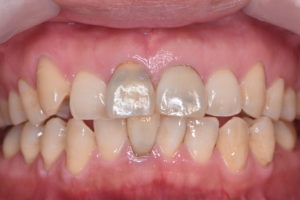

術前

主訴:神経を取った歯の色が気になる

所見:失活した右上中切歯に帯状の変色があり。既根管治療歯であり、根尖病変も存在する。歯根長は短く、残存歯質もかなり菲薄化している。